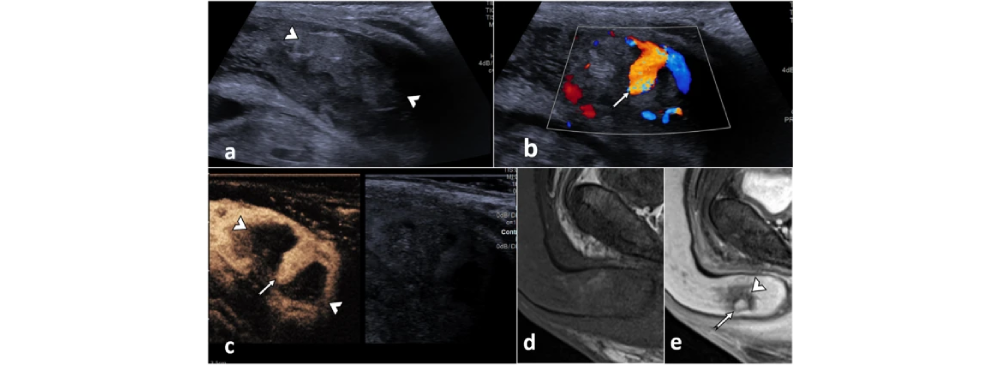

This test is completely non-invasive, safe, and painless. Using ultrasound waves, it allows radiologists to study how well blood circulates through the penile tissues both at rest and during stimulation. By analyzing this vascular performance, doctors can identify whether erectile dysfunction is linked to poor arterial inflow, venous leakage, or structural deformities such as Peyronie’s disease. The results provide clarity not only for men experiencing difficulties but also for specialists who want to design an accurate and personalized treatment plan.

During the procedure, a specialized ultrasound probe with Doppler imaging is used to study penile arteries and veins. A cooling gel is applied to the area for smooth imaging, and high-frequency sound waves are transmitted through the tissues. These signals create real-time images of blood flow. In some cases, to mimic a natural erection and get an accurate assessment, a small dose of medication may be injected. This allows doctors to evaluate vascular function under stimulated conditions, ensuring that no detail is missed.

• Visualization of blood flow in penile arteries and veins.

A Penile Doppler report format typically measures peak systolic velocity (PSV), end diastolic velocity (EDV), and resistive index (RI). Normal values usually include a PSV greater than 30 cm/s and minimal EDV, which indicates good arterial inflow and no significant venous leak. However, interpretation should always be done by a radiologist or urologist based on the patient’s overall condition.